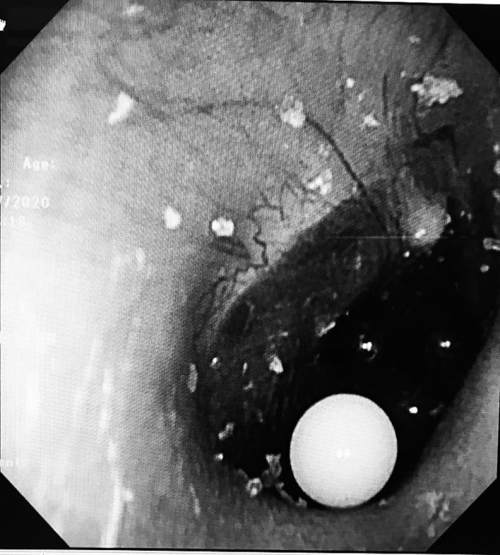

了解了情况后,医生为淘淘做了电子耳内窥镜检查,发现淘淘的右耳内有4颗彩色的小圆粒,位置都贴近了鼓膜,而且小圆粒填满了耳道。因为这是吸水弹珠,医生平时在门诊用的常规无创水冲洗法不可行,最终只能在全麻的情况下,为淘淘进行异物取出术。

耳道内发现的吸水弹珠

手术开始两分钟后,离鼓膜最远的白色弹珠被顺利取出。“第一颗取得还算顺利,但是取另外3颗就有点困难了,剩下的3颗小珠子相互挤压,与耳道壁及鼓膜紧密接触,我们只能用耵聍钩从珠子前方、下方寻找缝隙,从里往外将弹珠带出。”李莉萍说,经过一番努力,剩下的3颗弹珠也被顺利取出。